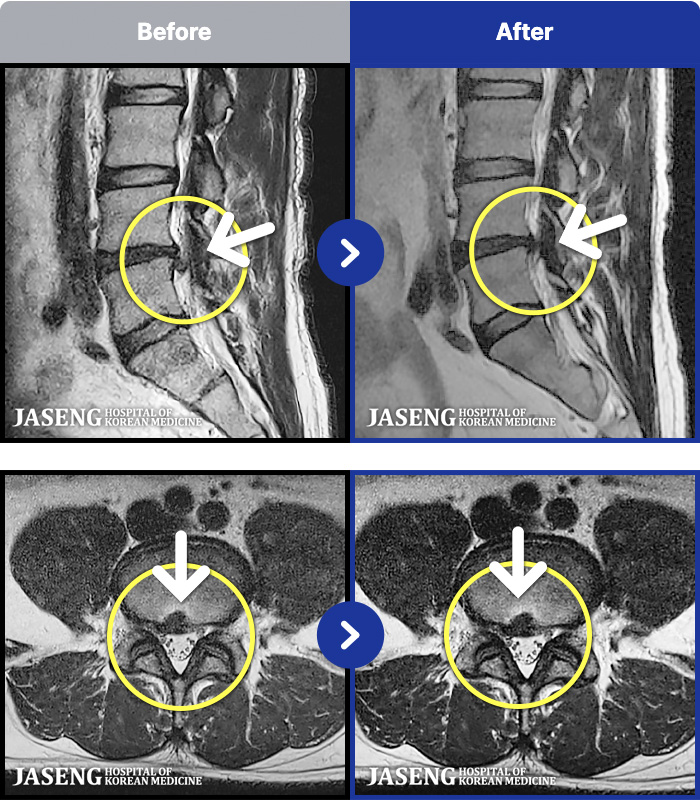

MRI ġ

1,237 MRI ũ ʸ Ȯϼ.